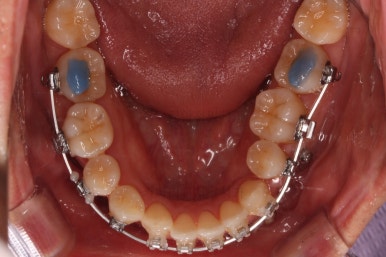

장치를 처음 부착했을 때의 입안 모습입니다.

아랫니가 해야될 작업이 많고 기간이 오래 걸리기 때문에 윗니는 최대한 늦게 장치를 부착하여 불편감을 최소화 하기로 했어요.

이번에 사용한 장치는 자가결찰 세라믹장치입니다. Empower clear(엠파워 클리어)라는 장치이고 흔히 많이들 알고계신 클리피씨와 동일한 유형의 장치에요.

아래 앞니 갯수가 이미 1개 모자라고 좌우 비대칭도 있고 아래앞니도 뒤로 당겨넣어야 하기 때문에 이를 1개 뽑았어요.

이를 뽑은 위치로 앞니도 뒤로 밀어넣어주고 좌우 균형도 맞춰주기로 했습니다.

이 뽑은 자리로 앞니를 쭈욱 밀어넣으며 비대칭도 맞춰주기 위해서 미니스크류(마이크로 임플란트)라고 불리는 작은 나사를 잇몸뼈에 식립했어요.

이를 지지대로 삼아서 치아를 움직이게 됩니다.